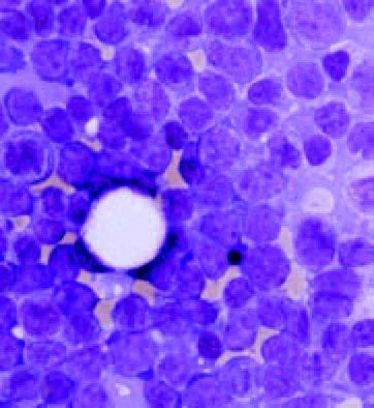

Gynäkologische Krebsvorsorge-Zytologie

Gynäkologische Krebsvorsorge-Zytologie